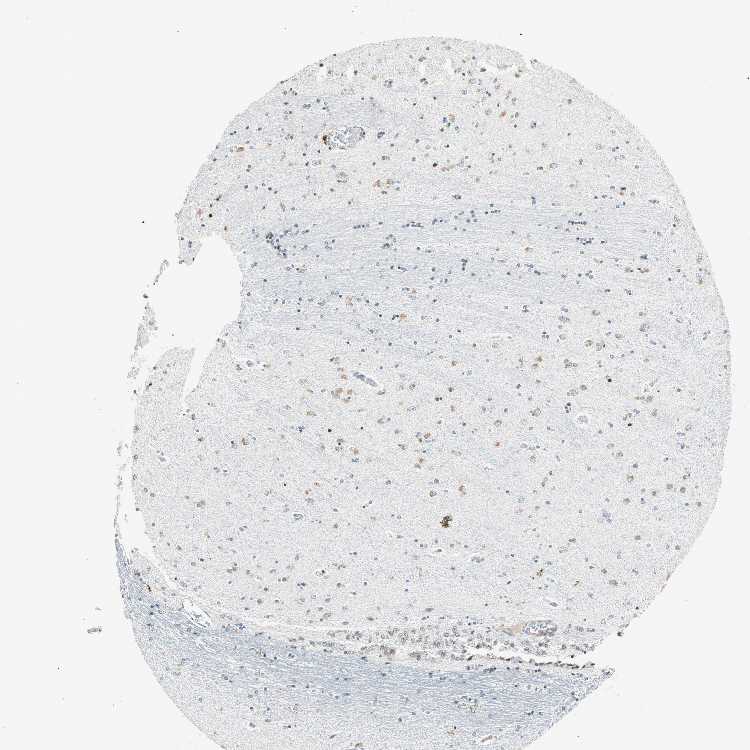

HIPPOCAMPUS - Antibody stainingi

Antibody staining in the annotated cell types in the current human tissue is reported as not detected, low, medium, or high, based on conventional immunohistochemistry profiling in selected tissues. This score is based on the combination of the staining intensity and fraction of stained cells.

Each image is clickable and will lead to virtual microscopy that enables deeper exploration of all samples and also displays staining intensity scores, fraction scores and subcellular localization as well as patient and tissue information for each sample.

Antibody HPA047213Antibody HPA062123Antibody CAB004506

Glial cells LowLowNot detected

Neuronal cells MediumNot detectedLow